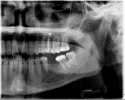

Болит 7-ка или 6-ка (на снимке верхние зубы). Врачи видят, что вытекло лекарство на 5-том, но говорят это не может болеть. Болит когда продувают между 6-тым и 7-мым.

Мне сделали 7-ой (без нерва). Сказали все сделали хорошо, но после этого на второй день опять начало болеть. Другой врач говорит, что это 7-мой плохо сделали и он болит. И, что это видно на снимке.

Что касается правильности лечения семерки, то можно сказать, что изъяны есть, но они очень незначительные — слегка нависающий край со стороны 6 зуба и небольшое размягчение зуба с противоположной стороны.